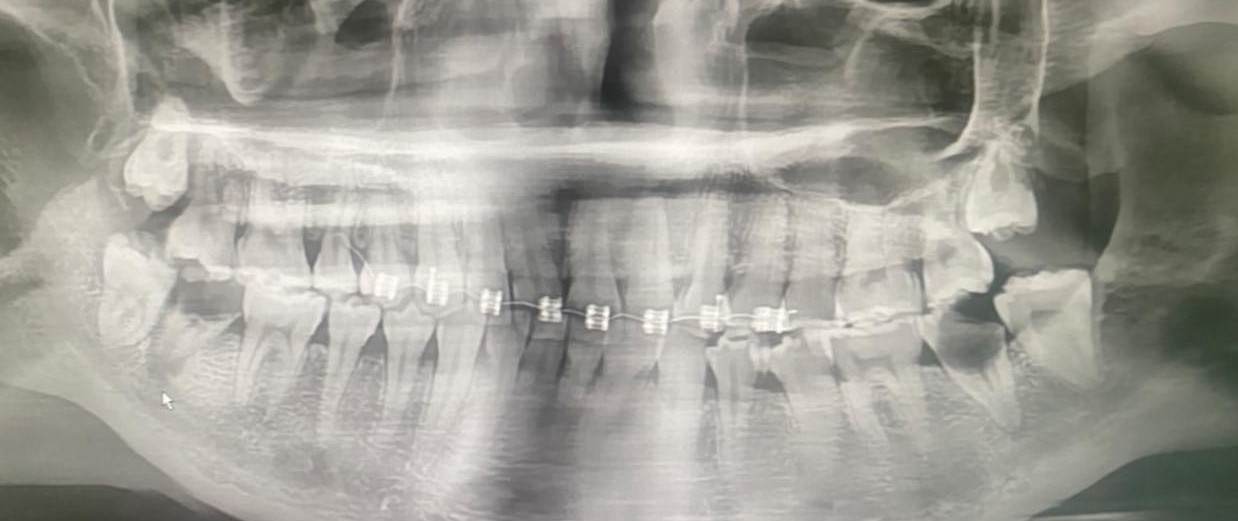

ก่อนหน้านี้เมื่อวันที่ 2 ต.ค. 68 ที่ผ่านมา ทพญ.สุรีรัตน์ สูงสว่าง ทันตแพทย์ และ รองผู้อำนวยการ โรงพยาบาลน่าน ได้ออกมาโพสต์เฟซบุ๊ก Sureerat Soongswang เตือนเคส ผู้ป่วย วัย 20 ปี จัดฟันแฟชั่น

ระบุว่า Line เด้ง จาก Somporn Keawnim หัวหน้าตึกหอผู้ป่วยวิกฤตหัวใจ เคสจริงที่หมอเจอ… น้องอายุเพียง 20 ปี เริ่มจากจัดฟันแฟชั่นในกรุงเทพฯ → ฟันผุ มีหนอง → เชื้อเข้ากระแสเลือด → จับเชื้อ Streptococcus gordonii → กลายเป็น เยื่อบุหัวใจติดเชื้อ (Infective Endocarditis)

สุดท้ายลิ้นหัวใจรั่ว ต้อง ผ่าตัดเปลี่ยนลิ้นหัวใจ ทั้งที่ยังอายุน้อยมาก 😢 ทั้งหมดนี้ เริ่มต้นแค่เพราะ “อยากจัดฟันแฟชั่น” อ่านไป ก็เออๆ น่ากลัวจริง ไปเอา forward line ที่ไหนมานิ ……

จัดฟันแฟชั่นทำมาจาก กทม. สัก 6 เดือนที่แล้ว ไอ หายใจไม่ค่อยสะดวก โทรหาแม่ แม่เลยพามารักษาที่น่าน อายุ 20 ปี แม่ให้ลาออกจากงานมารักษาตัวให้หายก่อน